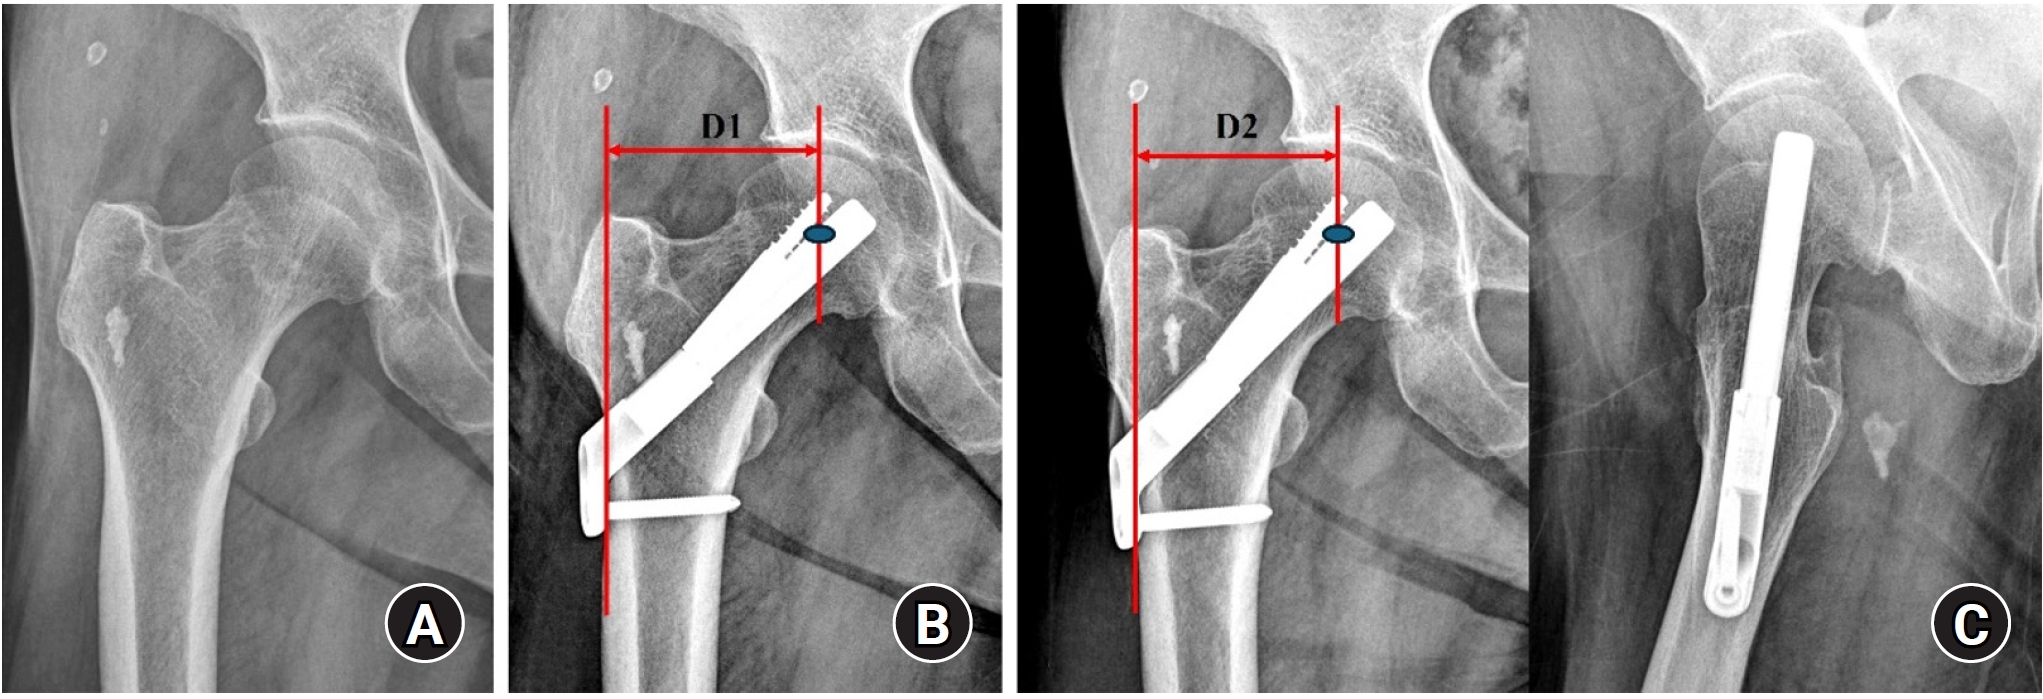

Fig. 3.

(A, B) An 86-year-old female patient with a stable right femoral neck fracture treated with a dynamic hip system. (C) Postoperative 1-year anteroposterior and axial radiographs show a well-healed fracture site and no complications related to the implant.

Fig. 3. (A, B) An 86-year-old female patient with a stable right femoral neck fracture treated with a dynamic hip system. (C) Postoperative 1-year anteroposterior and axial radiographs show a well-healed fracture site and no complications related to the implant.